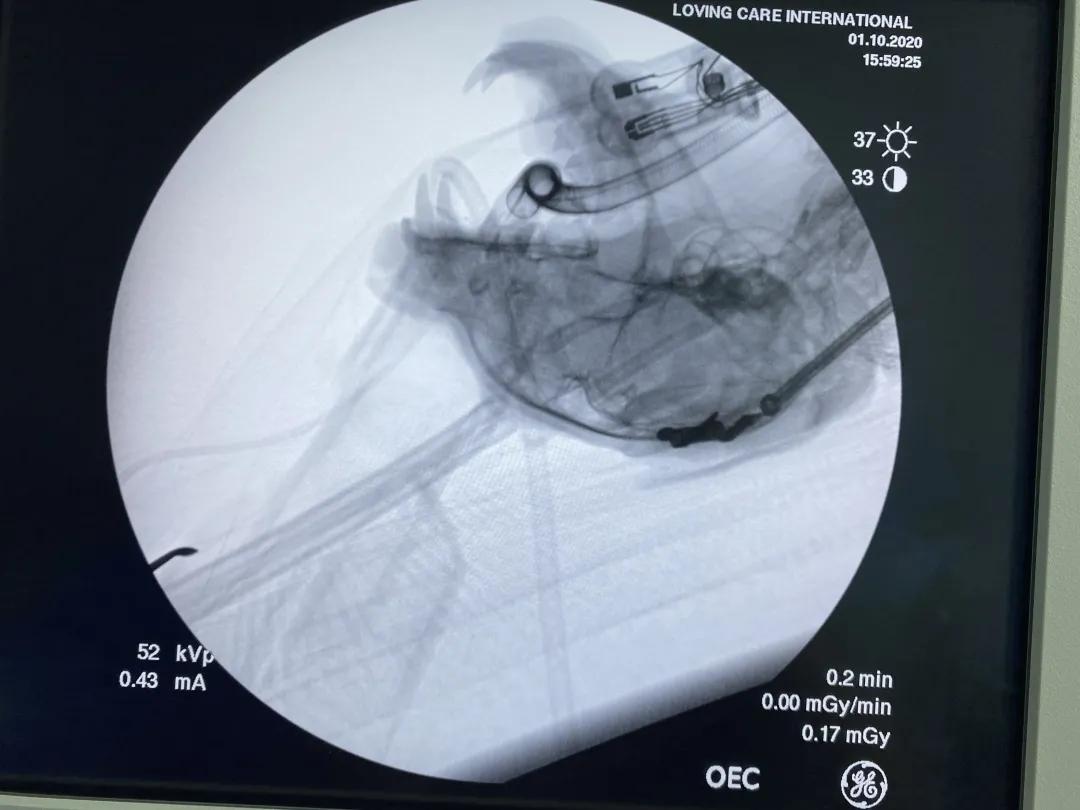

介绍一例小型犬食道异物的简单取出方法:

麻醉是关键,六公斤的西高地母犬,吞食猪骨头,在喉头的下方食道卡住了,由于价格的原因,家长想简单花费,不吸入麻醉,不插管,打算注射麻醉后让家长徒手取出,但是,担心犬麻醉有危险,犬有死亡的高风险,决定医院内麻醉取异物,最后经过中心医院护士的协助静脉注射舒泰和多咪静,大夫先保定头部,用手在食道卡骨头处固定异物,

缓缓上推骨头到咽喉部,长钳固定,用手调整适当位置,轻巧取出即可,术后输液,两小时后犬苏醒回家↓↓